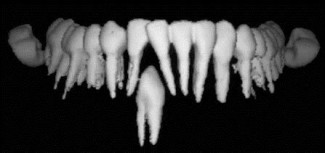

La guarigione porta alla scomparsa dell'area scura di radiotrasparenza ed avviene nell'arco di 6-12 mesi.

Se l'intervento di apicectomia ha avuto buon esito, dopo circa 6-12 mesi, ad un successivo controllo radiografico, l'area di radiotrasparenza deve essre completamente scomparsa. Il dente che ha subito un intervento di apicectomia, se correttamente ricostruito dal punto di vista conservativo o protesico, può a tutti gli effetti avere una prognosi a distanza simile a quella degli altri denti dell'arcata.